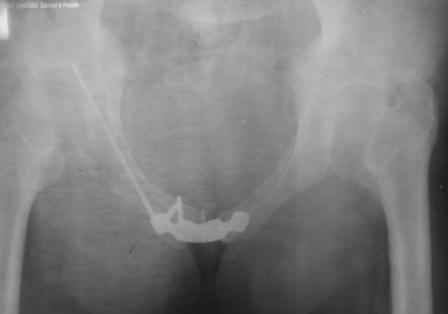

Уважаемый коллега! Огромное спасибо за рекомендации и иллюстрации! Задний комплекс, а точнее КПС не стал фиксировать т.к. само сочленение и суставная поверхность крестца целое, на кт-срезе имеет место краевой перелом и то не завершенный, учитывая что передняя связка КПС целая (а она сами знаете мошная)не стали фиксировать и клинический пациент не регировал, только КТ. Еще на Ваших фото винты вошли через кортикальный слой или ближе к перелому, а у нас вход в лон получилось прямо с мыса симфиза, т.е. перелом слева, винт зашел справа налево. Или это не принципиально?. С уважением Ерсин Жунусов.

положение и точка введения винта, при фиксации перелома горизонтальной ветви лонной кости и возможно acetabulum, определяется её анатомией. Корректная позиция и точка введения в приложенных картинках из руководства по внутреннему остеосинтезу.

С Уважением А.Миронов

1.jpg

64KB (66029 bytes)